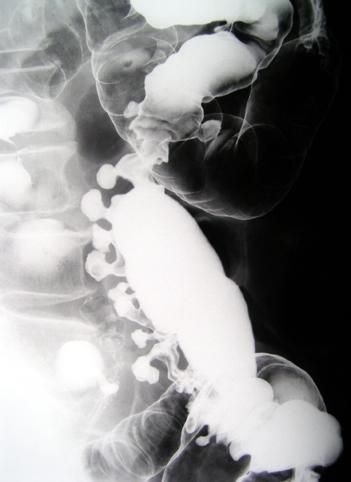

疾病(病理主体)的分类憩室/多发憩室

部位(按器官分)大肠/降结肠

检查方法X线